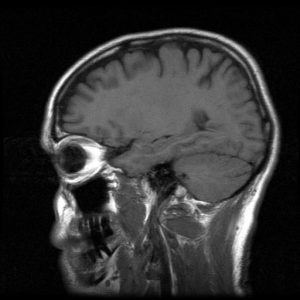

Mental health issues are much like the physical injuries you sustain in a car accident. Speak with a doctor or psychotherapist who can help you secure medication and/or the appropriate treatment and therapy for your specific situation.

Post-Traumatic Stress Disorder (PTSD): This is the most common health issue that crash survivors tend to experience. PTSD might present differently for victims and might not even fully manifest until several weeks after the crash. You may be experiencing PTSD if you are having recurring thoughts and flashbacks of the accident; experience emotional numbness or difficulty connecting with friends and family members; avoiding people, places and activities, especially those that remind you of the crash; are feeling a sense of hyper-vigilance or paranoia.

PTSD is not something that only soldiers in combat suffer. It can manifest in anyone who has experienced a traumatic event including crash survivors. Do not assume it will get better on its own. Seek help immediately.

Anxiety: Many victims tend to experience anxiety after a serious crash. Research shows that moderate and severe levels of anxiety can be present for several weeks or even months after an accident. Women are particularly believed to have high levels of persistent anxiety after a car accident. Anxiety can have a significant impact on one’s daily life. People with anxiety may face additional side effects such as panic attacks, sleep disorders, eating disorders, or even physical symptoms such as headaches, dizziness and muscle tension.

Depression: Depression is another serious mental health issue that car crash victims tend to experience. Some common symptoms include fatigue, lack of energy, feelings of guilt, lack of enjoyment in activities, suicidal thoughts, decreased focus or concentration, anger, irritability, inability to sleep and significant weight loss or gain.

Car accident victims may feel depressed because many lose their ability to work, exercise or enjoy everyday activities such as playing with their kids. Stress and worry about the financial repercussions of a car crash can also lead to depression. If you suspect you may be struggling with depression, it is imperative that you seek the counsel of a healthcare professional and receive the treatment you need.